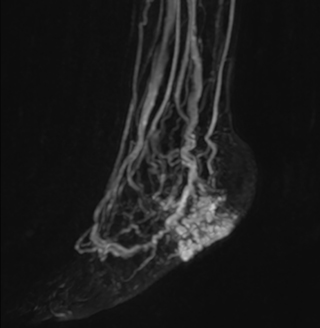

The subtractionless peripheral MR angiography shows improved vessel-to-background contrast and high resolution. Ingenia Ambition 1.5T.

Another example is the foot examination for diabetic patients, which has improved dramatically. “The forefoot is generally difficult to image with MRI because of the inhomogeneities that the toes create – it’s hard to obtain good fat saturation in that area. Here, mDIXON made a huge difference right away, we obtain much better image quality,” Dr. Peña says. “Using mDIXON, Compressed SENSE and the dS FootAnkle coil, we have been able to reduce the scan time, so that we can now also include an additional 3D STIR sequence to visualize both arteries and veins in the foot.”

Avila adds: “In addition, since most of these patients are in a significant amount of pain, it’s important to perform the examination as quickly as possible. With Compressed SENSE and mDIXON we have been able to reduce the scan time from about 45 minutes to just 15 minutes. Not only does this improve patient comfort, we see that it also helps us acquire images without motion artifacts, which is critical to making a confident diagnosis.”